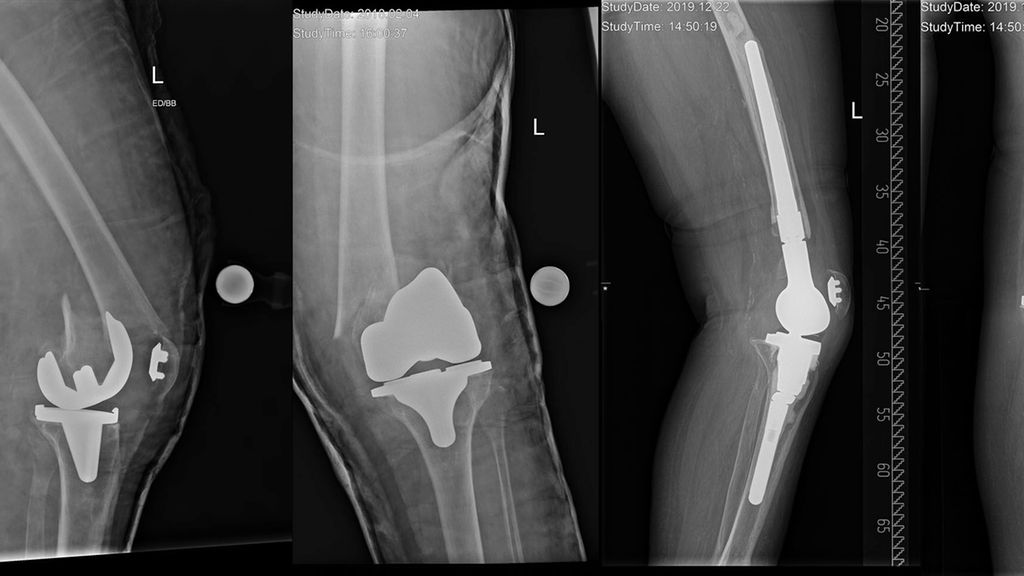

Abb. 1: Periprothetische Tibiafraktur vom Typ II nach Felix et al. (Mayo-Klassifikation). Die Autoren versorgten diese Fraktur mittels proximalen Tibiaersatzes sowie armierter Patellarsehne und führten einen kompletten Systemwechsel durch

Abb. 2: Periprothetische Femurfraktur vom Typ III nach Su et al. Die Autoren versorgten diese Fraktur mittels distalen Femurersatzes und kompletten Systemwechsels